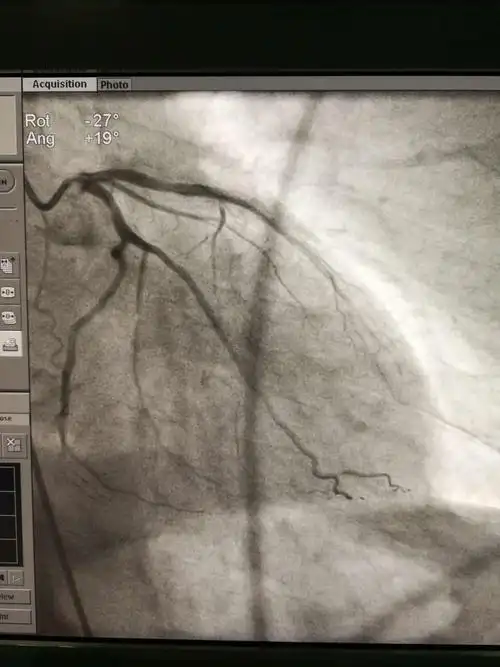

全脑血管造影术 冠脉造影术1例